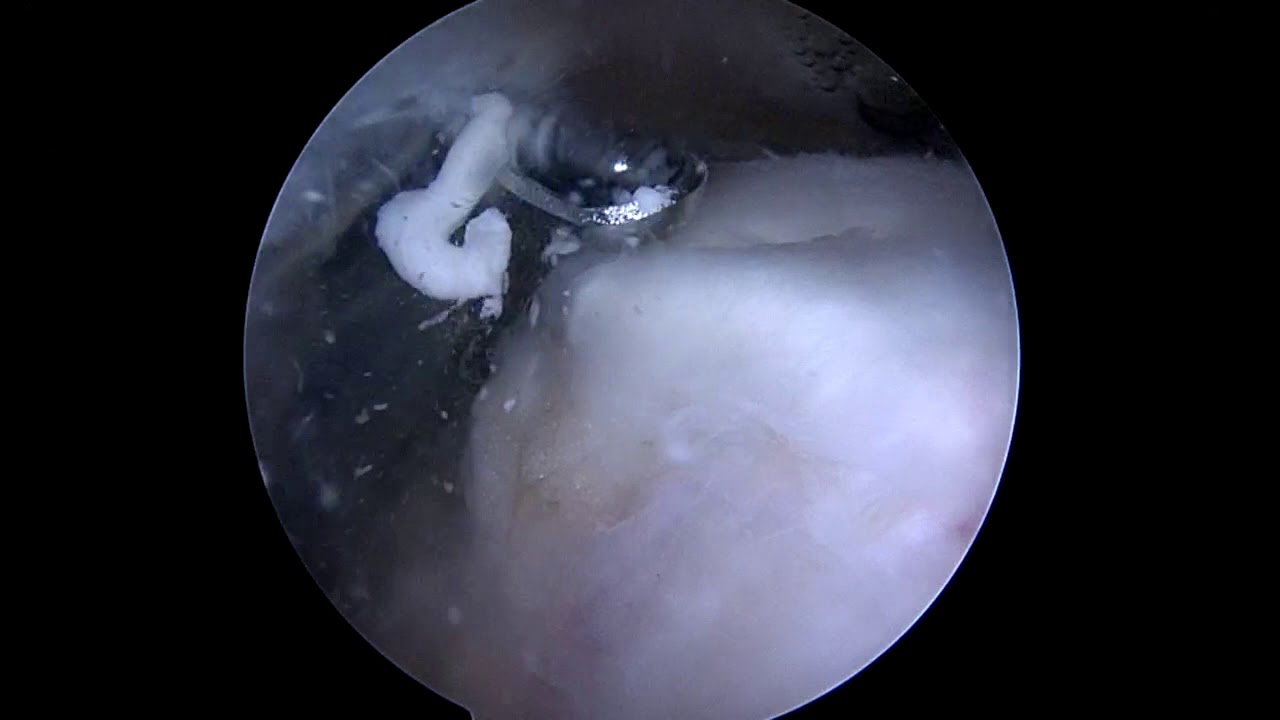

🖼 Hình 9 – Kỹ thuật barbotage dưới siêu âm

A: Siêu âm ổ vôi trục ngắn. B: Kim vào ổ vôi. C–D: Kỹ thuật barbotage. E: Canxi hút ra trong bơm tiêm

Kỹ thuật barbotage dưới siêu âm

🖼 Hình 10 – Canxi hút ra (calcium debris) sau barbotage

Dịch đục trắng như kem đánh răng (toothpaste-like) hoặc huyền phù sữa trong bơm tiêm

Canxi hút ra sau barbotage